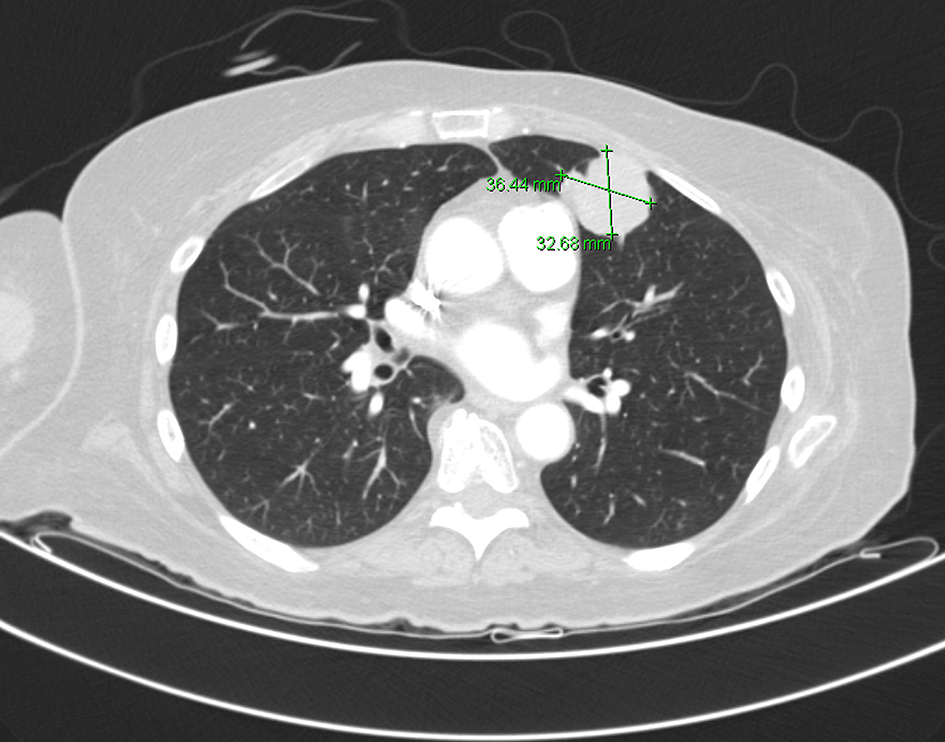

A 68-year-old Caucasian female sustained a fracture of the right humeral neck following a mechanical fall. She was scheduled for elective surgical fixation. Her past medical history was significant for 50 pack-year smoking history, chronic obstructive pulmonary disease (COPD), diabetes mellitus and hypertension. Pre-operative chest X-ray revealed an abnormal shadow of 4.1 cm on the left lung. Chest computer tomography (CT) scan revealed a 3.6 cm soft tissue mass in the anterior lingula (Fig. 1). Few days later, the patient presented to the emergency department with complaints of nausea, vomiting, diarrhea, weakness and dizziness. Laboratory workup showed sodium level 115 mmol/L, serum osmolality 248 mOsm/kg, urine sodium level 106 mmol/L, urine osmolality 554 mOsm/kg, and serum cortisol level 31 µg/dL (normal: 3.4 - 22.5). The patient had normal thyroid-stimulating hormone (TSH), blood urea nitrogen (BUN) and creatinine. Random blood glucose was 150 mg/dL. Serum uric acid was 3.2 mg/dL (normal 2.6 - 5.9). The hyponatremia was initially felt to be due to volume depletion in setting of decreased oral intake, use of hydrochlorothiazide, vomiting and diarrhea. However, her serum sodium (Na) level did not improve with volume repletion with normal saline but decreased even further to 114 mmol/L. Normal saline infusion was discontinued and fluid restriction was implemented. The serum Na level remained low despite fluid restriction and use of sodium chloride tablets and furosemide. Subsequently the patient received one dose of tolvaptan and her serum Na level increased to 125 mmol/L. Further management included continuing tolvaptan and oral sodium tablets and furosemide and gradual correction of Na level. Later lung biopsy was done and results showed small basophilic cells with a high nuclear to cytoplasmic ratio resembling small cell carcinoma (Fig. 2). However, immunohistochemical studies showed positivity for cytokeratin 5/6, p40, and CD56. TTF-1, chromogranin, synaptophysin, and neuron specific enolase were negative. A final diagnosis of BSQCC was made. The patient had brain magnetic resonance imaging (MRI) which showed no evidence of metastasis. The patient was not a candidate for surgical resection of the lung tumor due to underlying comorbidity and COPD. She was scheduled for outpatient follow-up and palliative care.

![]() Click for large image | Figure 1. CT scan of the chest shows left hilar mass measuring 4 cm. |